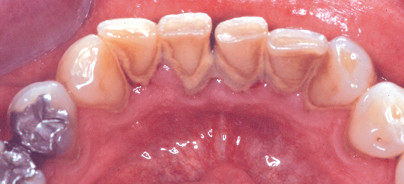

„Es hat keinen Sinn, sich einfach ein Gerät anzuschaffen, ohne einen Arbeitskurs mit einzuplanen“, betont Rothlauf. „Als ­erstes werden alle approximalen Oberflächen mit der Vector-Kürette instrumentiert. Das gelingt am rationellsten beginnend mit der oralen Seite im ersten Quadranten und erstreckt sich bis zum distalen Bereich der Bukkalflächen im zweiten Quadranten“, skizziert Rothlauf den Ablauf der Behandlung mit den drei Instrumenten Vector-Kürette, der gebogenen und geraden Vector-Sonde sowie den zwei neuen Instrumenten Paro-Lanzette sowie von Paro plus. Mit der vom Hersteller empfohlenen Behandlungssystematik „deckt das Vector-System, bestehend aus Vector Paro und Vector Scaler, den kompletten Bereich der Zahnstein- und Konkremententfernung im Rahmen der systematischen parodontalen Therapie ab“, fasst Braun zusammen.